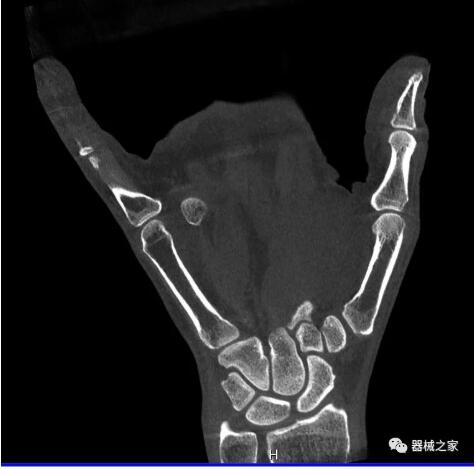

『大開(kāi)眼界』99%的人沒(méi)見(jiàn)過(guò)這樣的CT!

以下是這些“特立獨行”的CT所拍出來(lái)的圖像: